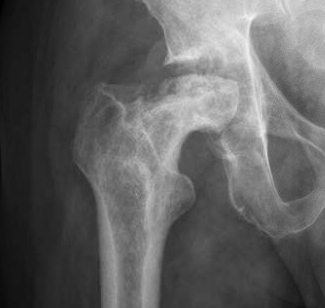

Crescent Sign

- subchondral collapse of the necrotic segment

- separation of subchondral plate from necrotic cancellous bone

Xray

Stage III: collapse / flattening femoral head with preserved joint space